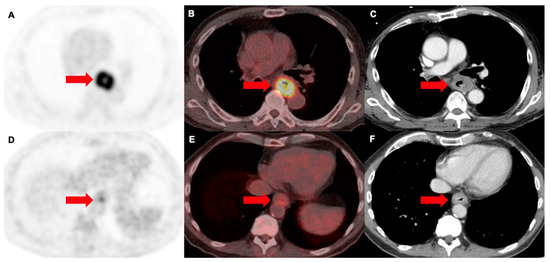

3.2. Prediction of Anatomical Disease Origin